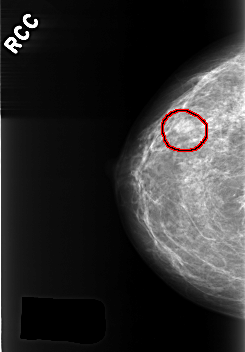

C_0363_1.RIGHT_CC

FILE: C_0363_1.RIGHT_CC.OVERLAY

TOTAL_ABNORMALITIES 1

ABNORMALITY 1

LESION_TYPE MASS SHAPE OVAL MARGINS CIRCUMSCRIBED

ASSESSMENT 3

SUBTLETY 4

PATHOLOGY BENIGN

TOTAL_OUTLINES 1

BOUNDARY